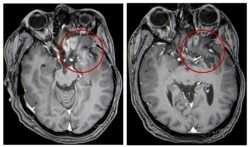

This combination of MRI images provided by the University of Alabama in April 2021 shows scans of a child with a brain tumor, before and after the treatment.

Average survival was just over a year. That is more than two times longer than in the past. As of last June, four of the patients were still alive at least 18 months after treatment.

Tests also showed high levels of specialized immune system cells in their tumors. This suggests that the treatment had created help needed from the body to attack the disease. No serious safety issues were seen.